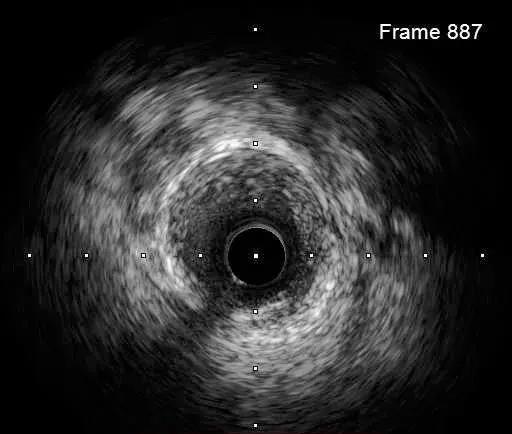

IVUS-1

远段直径2.2*2.4mm

对角支处局限血肿